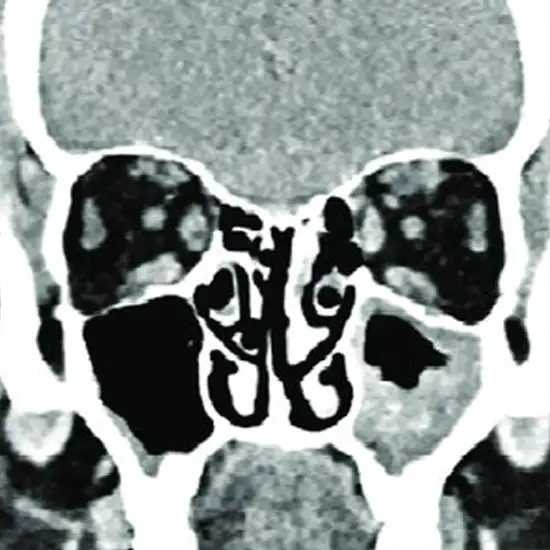

CECT Left Orbit is an imaging scan that is used to obtain clear images of the left eye orbit, left eye, and its surroundings. The contrast-enhanced computed tomography of the left orbit uses contrast media, and an x-ray beam to produce clear images of the left eye socket, left eye, and its surrounding area. Doctors recommend this scan to detect the broken/injured left eye socket area, and foreign objects in the left eye, and to diagnose injury, diseases, and congenital defects in the left eye.

For the procedure of CECT Left orbit, the Radiologist will inject you with contrast media which is a special dye before the examination through IV. The technologist will ask you to lie straight and still on the examination table. A rotating x-ray beam is used to create the image's left eye socket, left eye, and surrounding area.

CECT (Contrast Enhanced Computed Tomography) Left Orbits screening is a non-invasive radiology test used to evaluate the condition of the Left eye socket and surrounding tissue. CECT Left Orbits is done to look for the conditions of the eye socket and surrounding area.